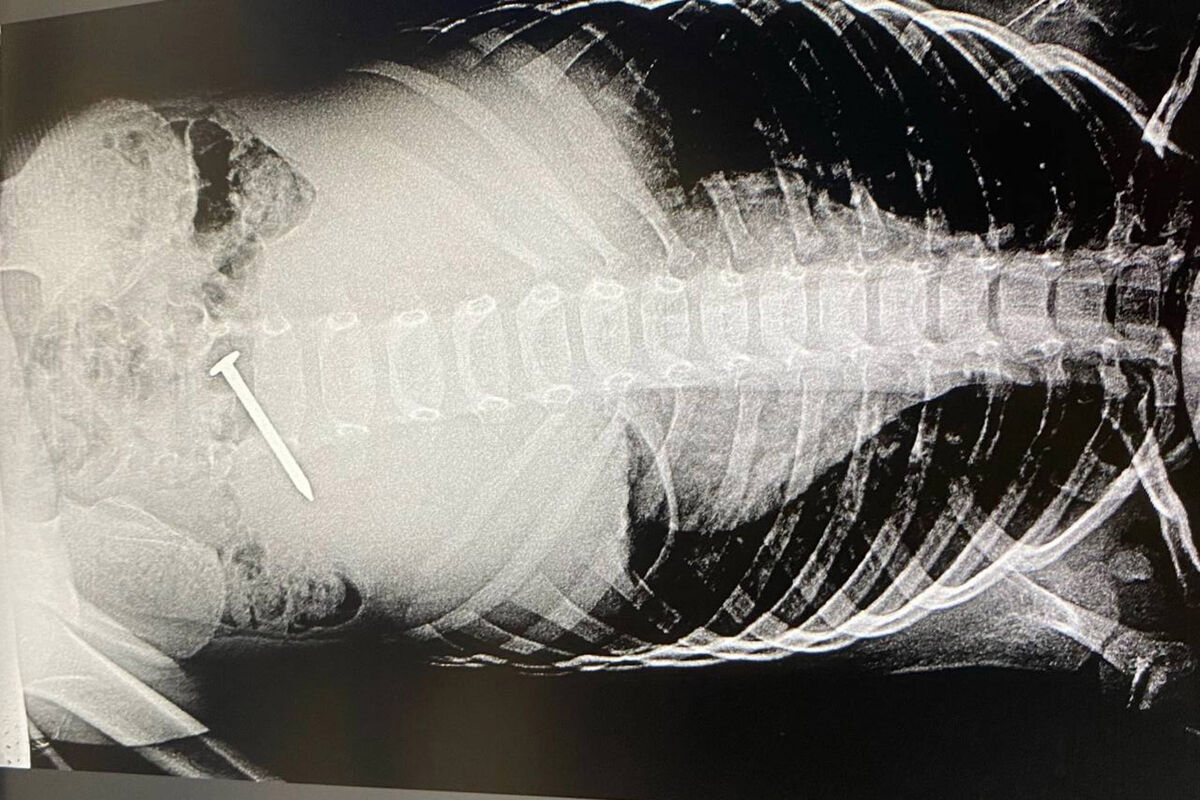

Российские врачи спасли трехлетнего ребенка, проглотившего гвоздь

В Татарстане трехлетний ребенок проглотил пятисантиметровый гвоздь

Врачи Альметьевской детской городской больницы спасли трехлетнего мальчика, который проглотил гвоздь. Об этом сообщили в пресс-службе медицинского учреждения.

Ребенок проглотил гвоздь во время игры, о чем позже рассказал матери. При этом инородный предмет пациента не беспокоил.

Мальчику провели диагностику, которая показала, что гвоздь расположился поперек двенадцатиперстной кишки.

«Гвоздь встал поперек, и можно было повредить стенку кишки, врачам удалось «стащить» инородное тело в желудок, что технически очень тяжело. Из желудка гвоздь извлекли корзинкой Дормиа (медицинский инструмент, предназначенный для захвата — «Газета.Ru»)», — поделились в пресс-службе больницы.

Четверо суток педиатры наблюдали за состоянием пациента и после контрольного обследования отпустили его домой.